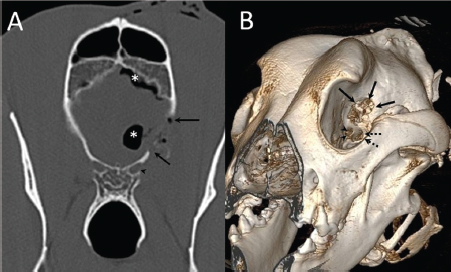

A 3-year-old female Great Dane was referred for acute onset behavioral changes (aggression and disorientation) of 2 weeks duration, and seizures from 24 hours prior to presentation. Physical examination revealed no abnormalities in body temperature, body condition score, heart rate, pulse quality, or cardiopulmonary auscultation. All lymph nodes were considered of normal size and no pain was elicited upon manipulation of the orbital, aural, or cranial musculature. Neither was there any history of dermatological or traumatic lesions in the eye, ear, or mouth. The neurological examination revealed the patient to be obtunded with decreased postural reactions and menace response worse in the left side. Neuroanatomic lesion localization was considered focal in the right prosencephalon with a possible increase in intracranial pressure. Hematological and serum biochemical analysis showed no abnormalities. Magnetic resonance imaging was performed using a low-field magnet (Airis Mate; Hitachi, Tokio, Japan). The study revealed a left-sided single frontal intra-axial lesion affecting gray and white matter adjacent to the internal capsule at the level of the optic canal (Fig. 1). The lesion presented signal homogeneity characterized by hyperintensity on T2W and FLAIR sequences and hypointensity in T1W sequences with peripheral enhancement after intravenous contrast administration (Fig. 1A and 1B). The lesion had a round shape with the greatest diameter of 2.84 cm. This enhancement was also recognized in the surrounding meninges following the brain surface following sulci. A small linear tract observed was directed dorsally from the lesion through the corona radiata (Fig. 1B). The lesion was associated with extensive perilesional vasogenic edema that worsened the mass effect characterized by a midline shift. The orbital and medial pterygoid muscles also showed an intense enhancement (Fig. 2). The wing of the presphenoid bone was thinner than the contralateral bone (Fig. 1B). A CT scan (Astelion 16, Toshiba, Tokio, Japan) was performed after MRI that allowed the identification of osteolysis in the presphenoid bone immediately dorsal to the orbital fissure (Fig. 1C). CT scan also revealed a hypoattenuating intra-axial lesion located in the left frontoparietal lobe together with diffuse hypoattenuation of tissues adjacent to the left optic nerve and the left pterygoid muscle. Finally, CSF analysis showed no abnormalities. On the basis of advanced radiological findings, the main differential diagnosis was an intracranial abscess due to the extension of the extracranial septic process through presphenoid bone. Because of rapid neurologic deterioration and suspected increased intracranial pressure, surgical excision was planned. A modified left rostrotentorial craniectomy was performed. Temporalis muscle and fascia were retracted, extending the incision cranially through the temporal line. Once the frontal and presphenoid bones were exposed an area of osteolysis was observed in the wing of the presphenoid bone immediately dorsal to the orbital fissure. The craniectomy (approximately 3 cm diameter) was centered on the osseous defect. A mucopurulent discharge presented immediately after the incision of the dura mater. A sample was collected for its microbiological study. The surgical site was flushed with sterile saline revealing the tip of a grass awn which was extracted from the brain parenchyma together with a small amount of purulent fluid (Fig. 3). After extensive flushing, the meninges were left open to allow drainage and the incision was closed as per routinely. Postoperative CT showed the correct location of the craniectomy and resolution of the abscess which was substituted by gaseous content but remained inside and on the dorsal surface of the frontal lobe (Fig. 4). Immediate postoperative therapy consisted of amoxicillin + clavulanic acid (Synulox 500, Zoetis Spain SL) 22 mg/kg PO, q8h; marbofloxacin (Marbocyl P80, Vetoquinol SA) 5 mg/kg PO, q24h; metronidazole (Flagyl 250, Sanofi-aventis SA) 15 mg/kg PO, q12h; prednisone (Prednisona Kern Pharma 30mg, Kern Pharma) 0.5 mg/kg PO, q12h; tramadol (Tramadol retard Combix 100 mg, Laboratorios Combix S.L.U) 2 mg/kg PO, q8h; famotidine (Famotidina Normon 40 mg; Laboratorios Normon SA) 0.7 mg/kg PO, q24h; and phenobarbital (Phenoleptil 100 mg, Le Vet BV) 2.5 mg/kg PO, q12h. Cultured samples were positive for Pseudomonas aeruginosa sensitive to ciprofloxacin, imipenem, and amikacin among other antibiotics. Based on these results, antibiotic therapy was changed to ciprofloxacin (Ciprofloxacino 500, Laboratorios Normon SA) 10 mg/kg PO, q12h and metronidazole 15 mg/kg PO, q12h for 2 months. Prednisone, tramadol, and famotidine were withdrawn and phenobarbital was maintained at 2.5 mg/kg q12h. Six-month post-operative revision magnetic resonance revealed no signs suggesting the existence of an inflammatory process (Fig. 5). In the area where the abscess had been located, a fluid-filled cavity suggesting being CSF was observed. One year follow-up revealed the patient had seizures every 3 months with neurological examination remaining normal. The patient died 2 years later of unrelated causes.

Fig. 4. (A) Transverse and (B) 3D reconstruction postoperative CT images. Note increased defect on the presphenoid bone (arrows) immediately dorsal to the optic canal (arrowhead) and orbital fissure (dotted arrow). Also, note the presence of hypoattenuating content inside and over the dorsal surface of the frontal lobe (asterisks) compatible with air.

Fig. 5. (A) Transverse T2-weighted, (B) transverse post-contrast T1-weighted image, and (C) dorsal post-contrast T1-weighted image obtained 6 months after surgery. Note the absence of any contrast enhancement and residual lesion connecting the lateral ventricle (arrows). Also, note the defect in the presphenoid bone (arrowheads in C).